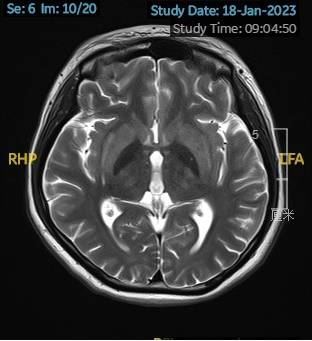

2023.02.09颅脑MR平扫示双侧基底节区及桥脑异常信号,考虑渗透性神经脱髓鞘综合征可能,脑桥部病灶较前范围增大,请结合临床,见图2。

图2 2023.02.09颅脑MR成像示双侧基底节区及桥脑见对称性片样长T1长T2信号,FLAIR呈高信号,较2023-01-18MR所示脑桥病灶范围增大。脑室、脑池、脑沟、脑裂未见明显异常。中线结构居中。